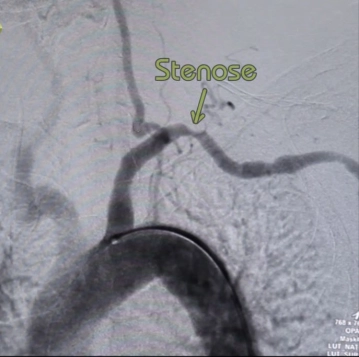

Estenose ou oclusão da artéria subclávia apenas em casos de sintomas claramente atribuíveis/hipoperfusão do braço: